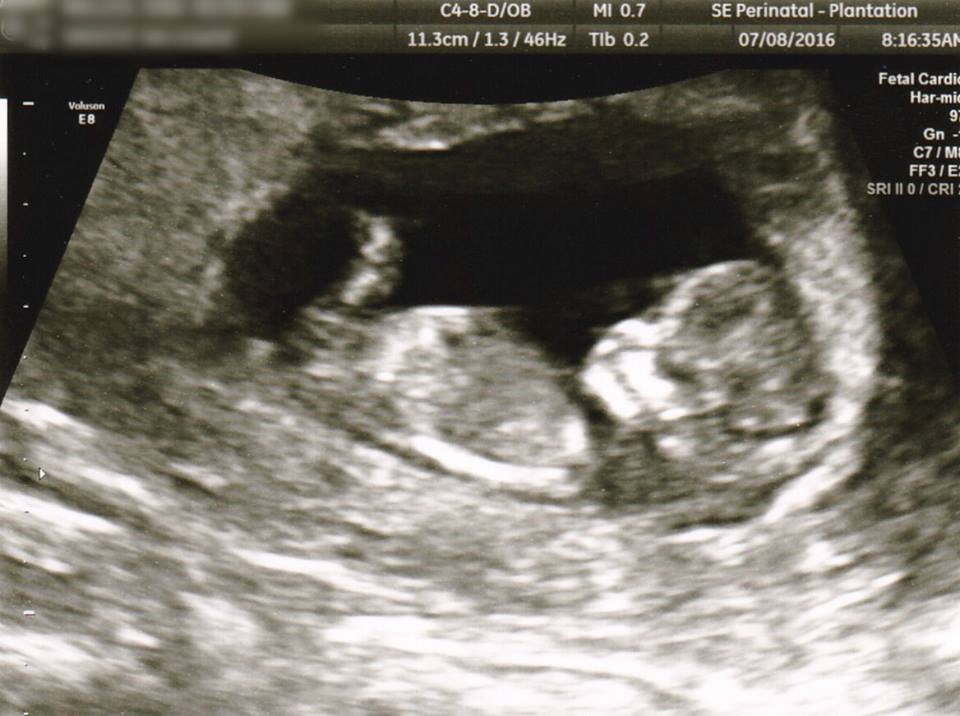

Baby Chris is Nine Weeks Old

One week into the fetal period, Baby Chris is exhibiting new behaviors. According to the Endowment for Human Development, “thumb sucking begins and the fetus may swallow amniotic fluid. The fetus can also grasp an object, move the head forward and back, open and close the jaw, move the tongue, sigh, and stretch. By 9 weeks, the nerve receptors in the face, palms of the hands, and soles of the feet can sense and respond to light touch. Following a light touch on the sole of the foot, the fetus will bend the hip and knee and may curl the toes.”

Baby Chris is about an inch and a half long from crown to rump. He or she has developed eyelids, which are fused together. Vocal chords are also developing at this point, as are the uterus and ovaries if Baby Chris is female.